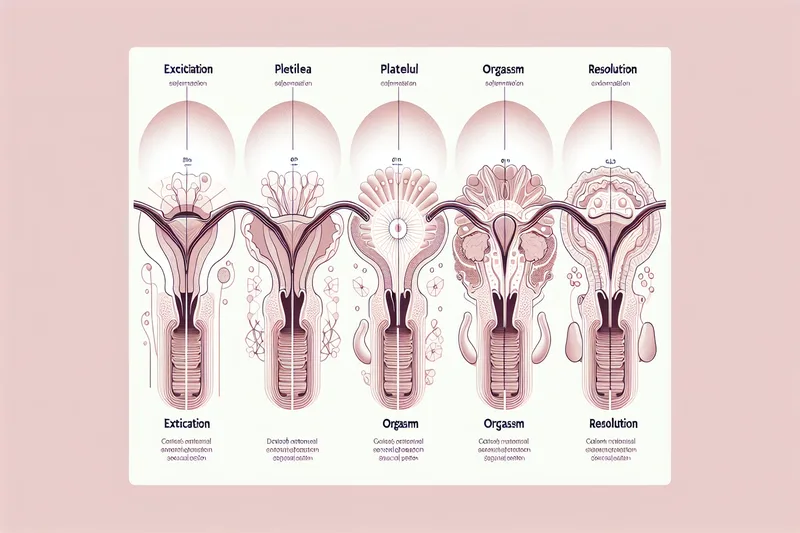

L'orgasme féminin

Guide complet sur les phases de la réponse sexuelle, les effets sur le cerveau et le rôle du clitoris dans l'orgasme.